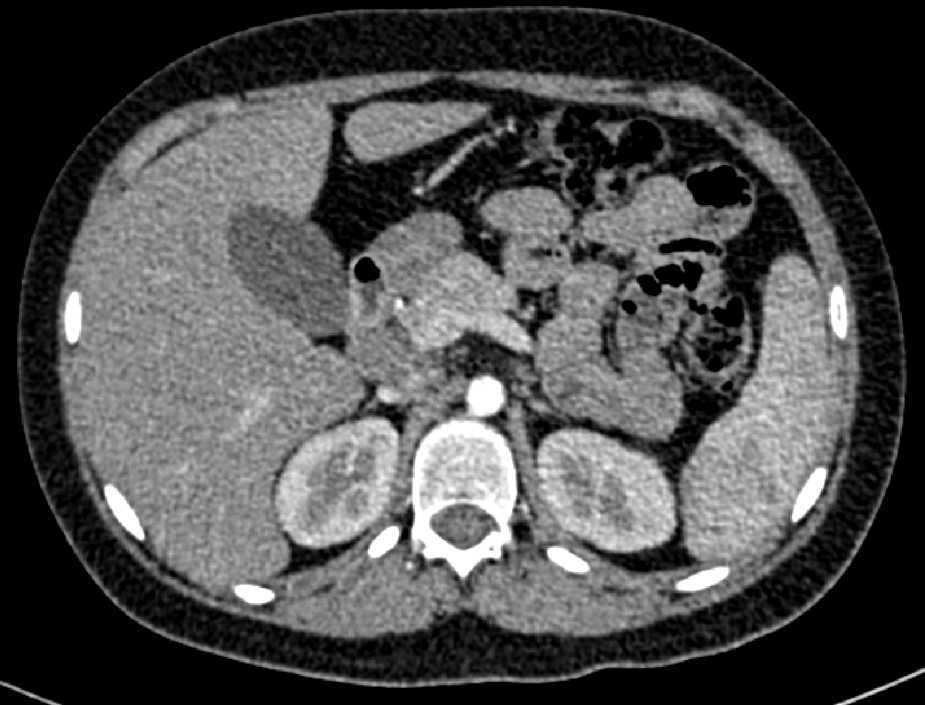

En la tomografía computada de tórax y abdomen se observaron conglomerados ganglionares en mediastino, mesenterio, retroperitoneo y región inguinal, infiltrado micronodular difuso bilateral, hepatomegalia, esplenomegalia, así como litiasis renal derecha (Fig. 3).

El presente caso corresponde a un adolescente de sexo masculino con un cuadro clínico compatible con sarcoidosis infantil de inicio tardío, con grave afección del estado general que le llevó a la caquexia. También presentaba daño pulmonar, hepatomegalia, esplenomegalia, adenopatías múltiples, eritema nodoso y masa escrotal. Se realizó el protocolo de abordaje diagnóstico para pacientes con hepato-esplenomegalia, el cual permitió descartar varias enfermedades infecciosas, como tuberculosis, micosis sistémicas, sífilis e infección por virus Epstein Barr (VEB) y virus de la inmunodeficiencia humana (VIH), además de otras causas de síndrome infiltrativo, como leucemias, linfomas, tumores metastásicos y linfohistiocitosis hemofagocítica, mediante los estudios de tomografía computada y las biopsias de médula ósea y de ganglio linfático. Se descartaron, incluso, vasculitis sistémicas y otras enfermedades autoinmunes, así como los tumores testiculares de la adolescencia con base en los hallazgos del ultrasonido testicular y con los niveles normales de marcadores tumorales como alfa-feto proteína y beta-gonadotropina61.

A su ingreso se detectó insuficiencia respiratoria crónica tipo I, sin repercusión cardiovascular, con hipoxemia, normocapnia e hiperlactatemia. La radiografía de tórax mostró infiltrado micronodular y reticular difuso con adenopatías hiliares bilaterales, concordante con el Estadio II de la clasificación de la American Thoracic Society para sarcoidosis torácica. Así mismo, la espirometría y la pletismografía reportaron una disminución de la relación VEF1/FVC, compatible con una neumopatía de patrón restrictivo leve como se ha descrito en las dos primeras etapas de la sarcoidosis pulmonar, que se normalizó después del tratamiento con prednisona.